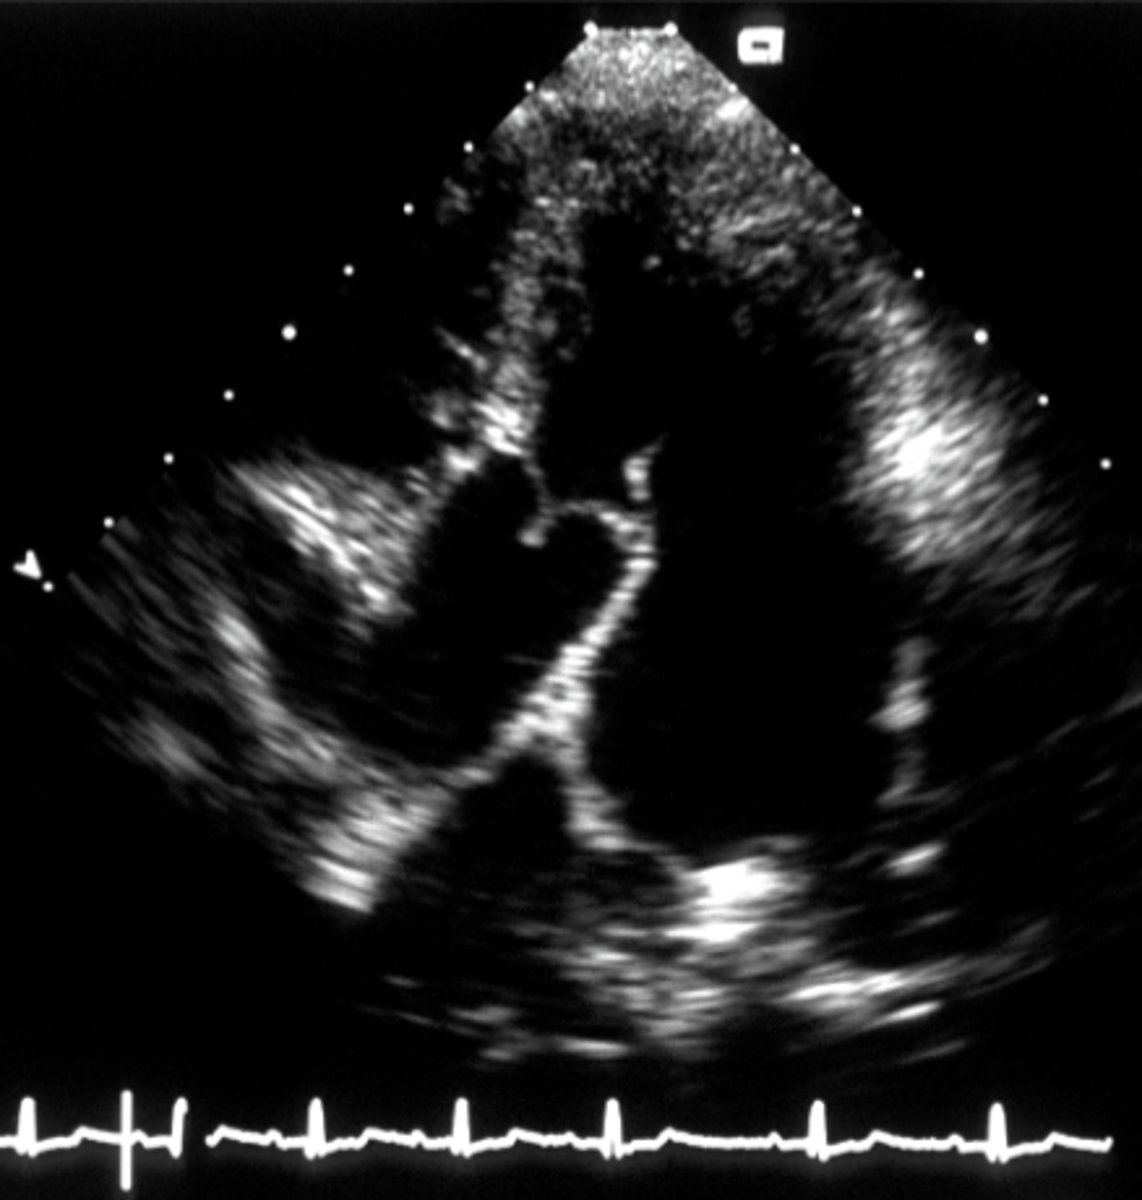

right parasternal long axis view

used for four chamber or five chamber view when the dog in on their right side

For right parasternal long axis view, the four chamber view focuses on the _______ valve while the five chamber view focuses on the _______ valve

mitral; aortic

what is the right parasternal long axis view used to evaluate?

LV outflow, systolic function, and valve function